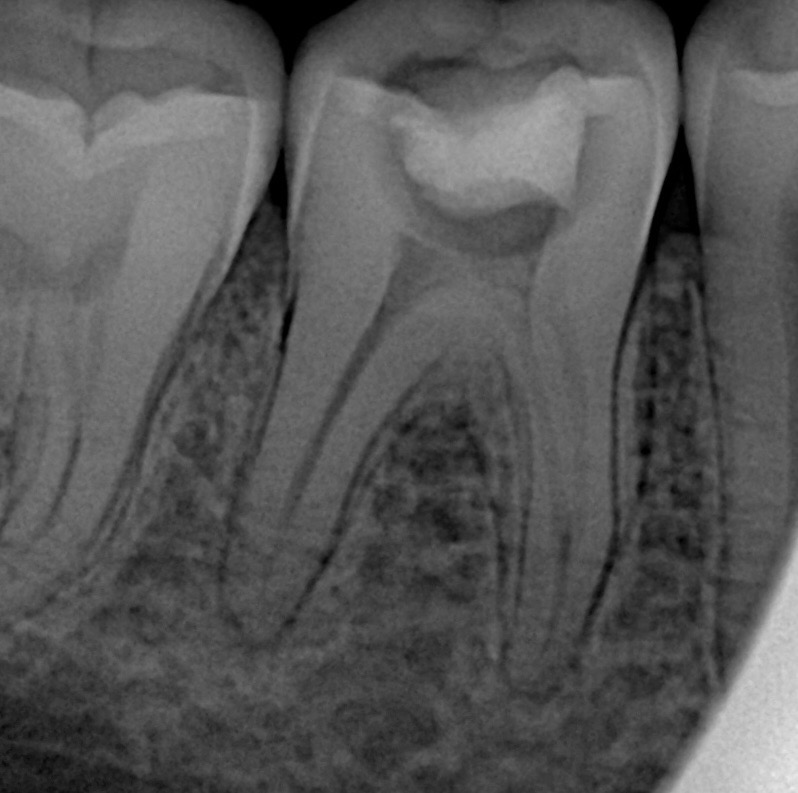

A 24-year-old patient presented with spontaneous pain on biting and tenderness localized to the mandibular right first molar (#46). Clinical examination revealed a large defective composite restoration with underlying recurrent caries. The tooth tested symptomatic irreversible pulpitis with normal periapical findings. Preoperative periapical radiograph showed deep recurrent caries approaching the pulp with no periapical radiolucency.

- Working length established using apex locator and confirmed radiographically.

- Post-operative radiograph confirms dense 3D obturation to working length.